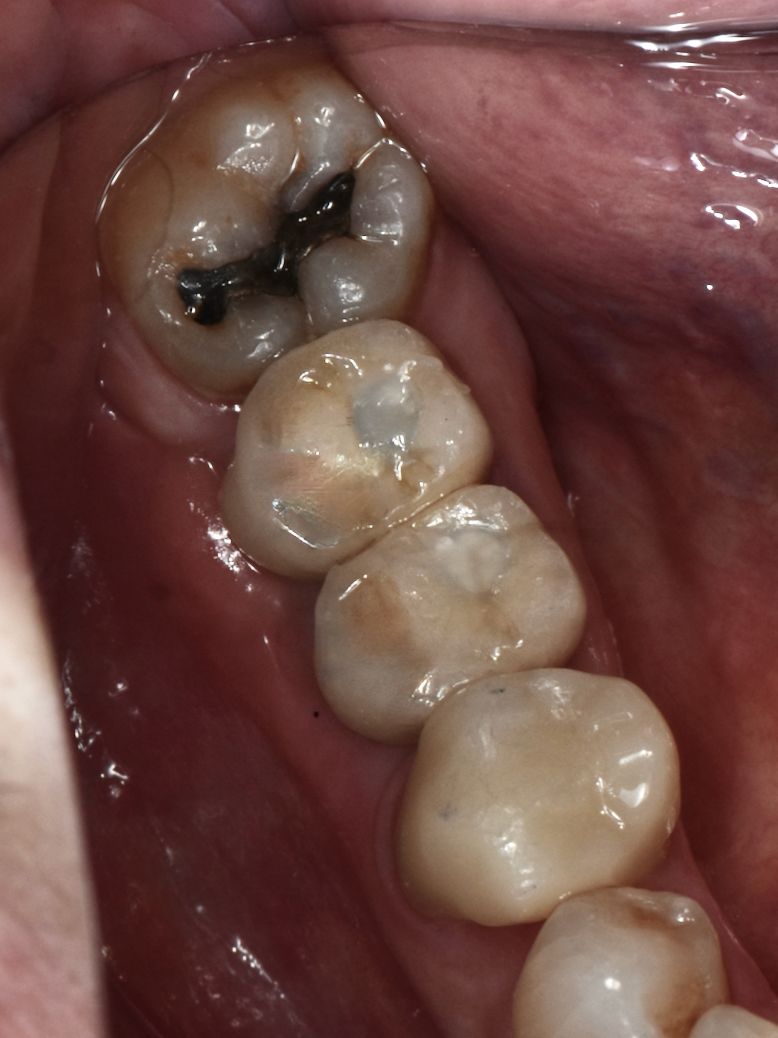

Traumatismo dental

PROMOCIÓN, 50% DE DESCUENTO EN TU SEGUNDO IMPLANTE

Implante dental

Los implantes dentales son la forma mas estética y funcional de sustituir una diente perdido, ya sea por caries, enfermedad periodontal, traumatismo o agenesia. Lo mas importante para que este tratamiento sea exitoso es su correcta planeación.